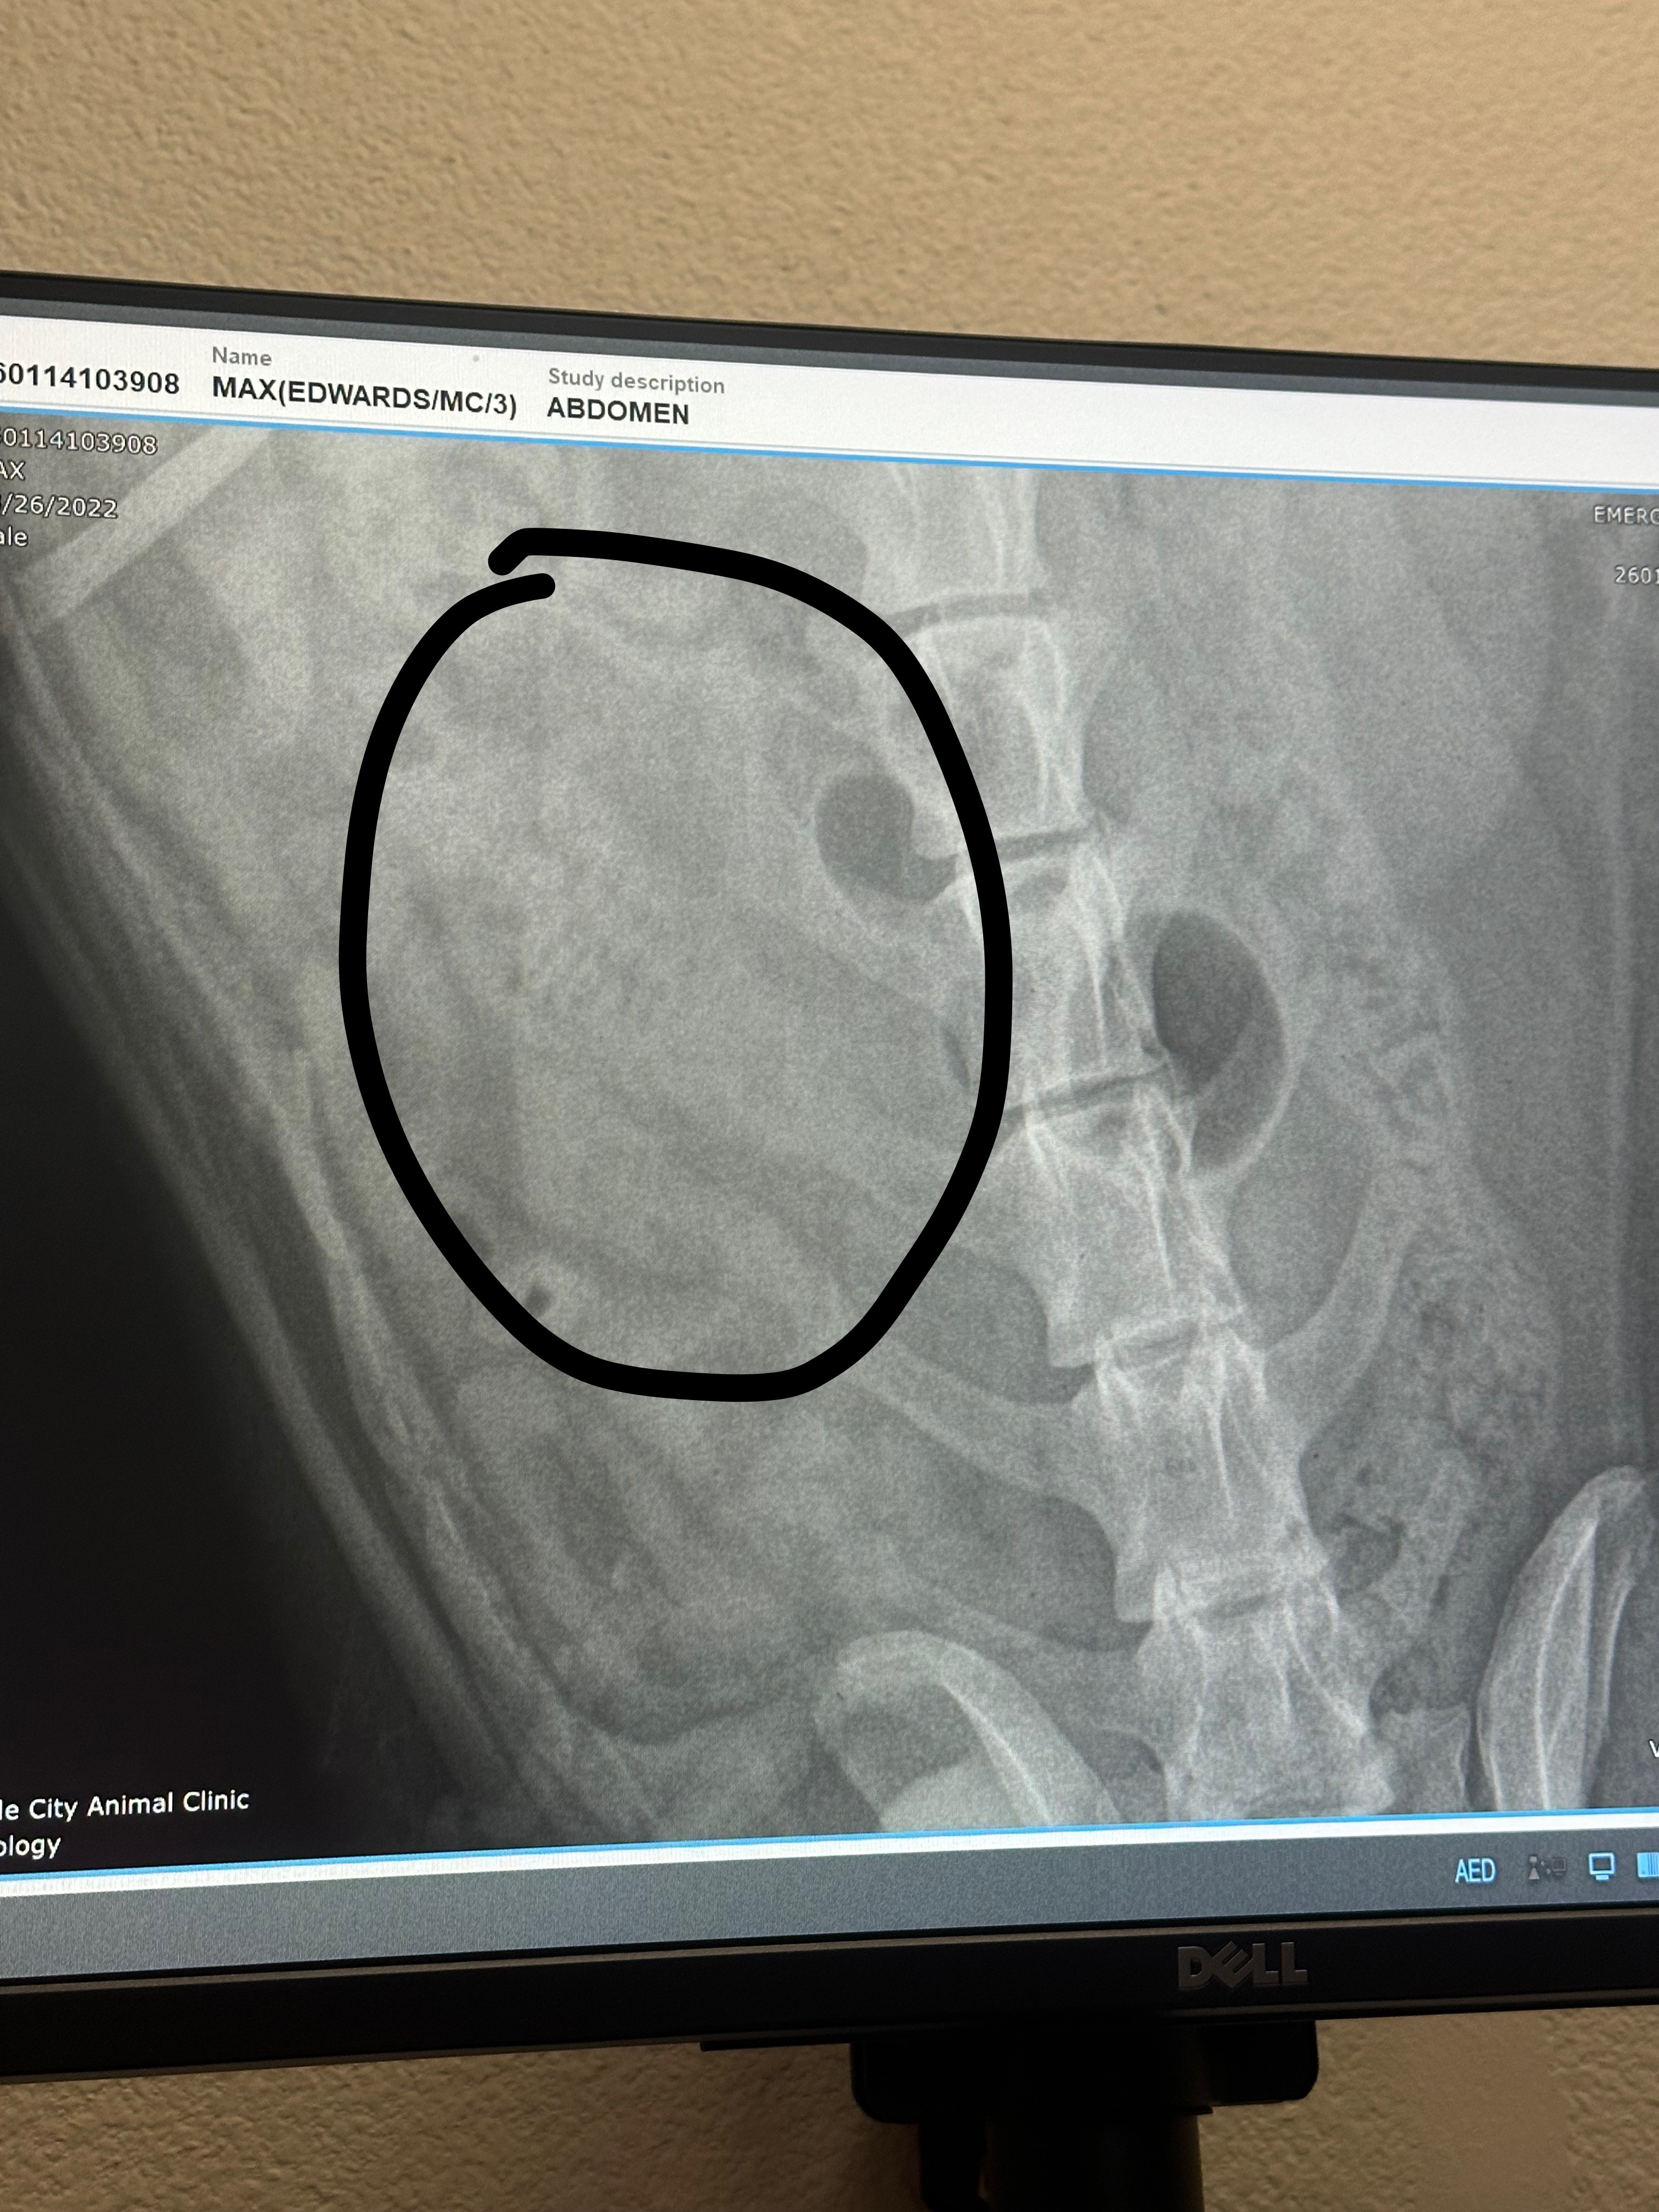

Our sweet Max is currently facing an emergency medical situation after accidentally eating a corn on the cob. Unfortunately, it became lodged in his intestines and cannot pass on its own. The only option to save his life is immediate surgery.

The medical team at Dade City Animal Clinic has confirmed that surgery is necessary to remove the obstruction and prevent further complications. As you can imagine emergency surgery and hospitalization come with unexpected and overwhelming costs.